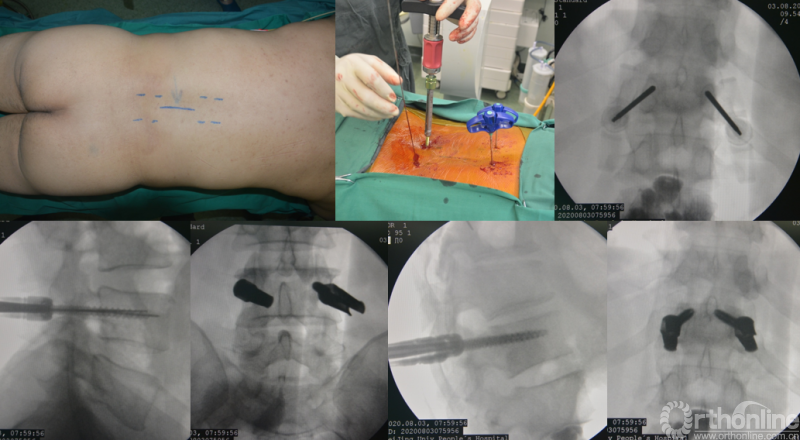

为进一步减少创伤,获得更好的综合疗效。骨采用经皮内固定的微创杂交技术,暨经皮内固定结合小切口分离手术,手术失血900ml,术后7天出院。

术中资料

手术视频:http://res.orthonline.com.cn/video/SSZH.mp4